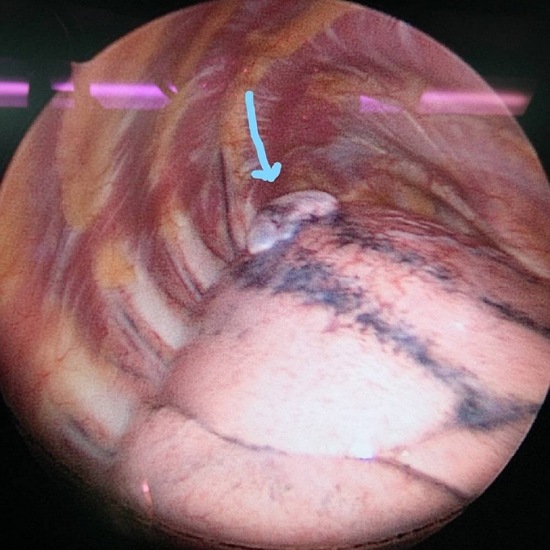

โดยรักษาด้วยการผ่าตัดภาวะลมรั่วในเยื่อหุ้มปอดขณะมีประจำเดือนนั้น ในปัจจุบันภาวะลมรั่วในเยื่อหุ้มปอดสามารถทำได้โดยการผ่าตัดผ่านการส่องกล้อง (Video Assisted Thoracoscopic Surgery; VATS) หรือ การผ่าตัดเปิดแบบดั้งเดิม (Open Thoracotomy)โดยเป้าหมายของทั้ง 3 วิธี ได้แก่ 1. จัดการสาเหตุของลมรั่ว โดยการหาสาเหตุของลมรั่วจากปอดให้พบ เช่น ถุงลม (blebs, bullae) ที่แตกและทำการซ่อมแซมหรือตัดบริเวณส่วนนั้น 2. การทำสร้างพังผืด (Surgical Pleurodesis) ระหว่าง Parietal และ Visceral Pleura เพื่อทำให้เกิดการอักเสบ เพื่อลดอัตราการกลับมาเป็นซ้ำ โดยสามารถทำได้หลายวิธี เช่น การลอกเยื่อหุ้มปอด (Pleurectomy) หรือ การขูดบริเวณเยื่อหุ้มปอด (mechanical pleural abrasion ) และใส่สารเคมีบริเวณเยื่อหุ้มปอด (Chemical Pleurodesis) และ 3. ตัดบริเวณกระบังลมที่มีการกระจายตัวของช็อตโกแลตซีสต์ (Resection of Fenestrated Diaphragm) โดยผลของการผ่าตัดเปรียบเทียบระหว่างการผ่าตัดเปิดกับผ่าตัดส่องกล้องพบว่าผ่าตัดส่องกล้อง สามารถลดภาวะเสี่ยงได้ ดังนี้ 1. ลดภาวการณ์ปวดหลังจากการผ่าตัด 2. ลดระยะเวลาการนอนโรงพยาบาล และ3.ลดภาวะแทรกซ้อนของการผ่าตัด